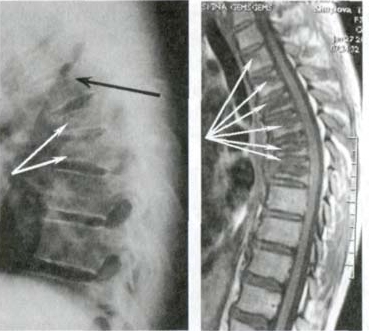

Tutte le articolazioni sono soggette a usura, ma proprio nella colonna la mancanza di terminazioni nervose può mascherare cambiamenti catastrofici. La compressione del nervo sciatico da un’ernia è un processo doloroso, che inizia con lieve dolore alla parte bassa della schiena e si diffonde alle gambe con formicolio e intorpidimento, fino al completo blocco. Il danno progressivo porta alla paralisi delle gambe, rendendo quasi impossibile recuperare il controllo

Guardate questa radiografia. È la colonna vertebrale di una persona di soli 44 anni, ma sembra quella di un vecchio. Una volta questi danni si riscontravano dopo i 60 anni, ma oggi è comune per chi ha appena più di 40 anni. Questi cambiamenti progrediscono con l’età, e ignorarli significa rischiare la perdita completa della mobilità!

Ma sono particolarmente pericolosi i dolori alla schiena — a causa della struttura particolare delle cartilagini e dei dischi intervertebrali, l’usura completa delle cartilagini avviene fino a 3-4 volte più velocemente!

— Pensateci bene! Solo in poche settimane la malattia può progredire così rapidamente che la compressione del nervo causata dall’ernia diventa irreversibile, e qualsiasi recupero dei dischi vertebrali non avrebbe più senso! Il nervo non potrà più essere ripristinato e NON AVRÀ PIÙ SENSO CERCARE DI RIPRISTINARE I DISCHI VERTEBRALI! E non avrete più scelta — SOLO LE STAMPELLE E LA SEDIA A ROTELLE PER TUTTA LA VITA!

Una delle poche soluzioni che la medicina può offrire è un’operazione complicata e rischiosa per rimuovere l'ernia e inserire perni metallici! Ma pensateci bene! Anche i migliori chirurghi ammettono che un intervento sulla colonna vertebrale è una misura estremamente sconsigliata e pericolosa, CHE PORTA SPESSO A PROBLEMI ANCORA PIÙ GRAVI, INFEZIONI, CONTAGI, COMPLICAZIONI E PERSINO ALLA MORTE!